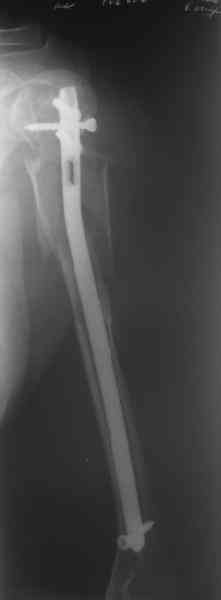

Здесь нет необходимости в серкляже. Вмешиваться на промежуточных

отломках приходится, если есть угроза перфорации кожи, или

промежуточный отломок попал в фасцию, как пуговица в петлю. В

приложении сегментарный оскольчатый перелом плеча в проксимальном

отделе, фиксированный больщеберцовым стержнем. Как видите, обошлось

без серкляжа. Функция полная.